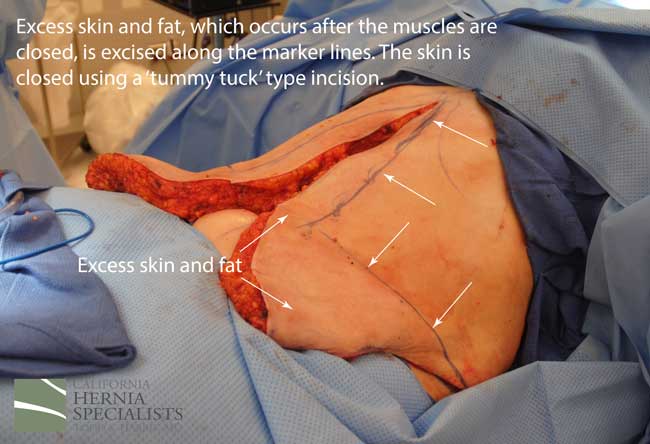

This technique requires more surgical time, recovery time, and usually several days in the hospital. However, this patient chose to proceed with the open hernia repair. Below are some of the pictures from his surgery as well as post operative CT scan image and photos of the patient.

Instead we discussed open hernia repair with a large incision to repair the damaged muscle and to remove excess skin and fat once the muscle was repaired. Below are a number of pictures including before and after photos, as well as photos taken during her surgery.

Because this patient had failed two prior surgeries, we performed a complex open hernia repair on him. This repair included a technique called ‘component separation’, where the oblique muscles on the sides of the abdomen, are partially released, or cut, to allow the rectus muscles to be pulled back together in the middle of the abdomen.

Since the abdominal muscles were weakened, we placed a sheet of biologic mesh under the muscle in the middle at the area of the hernia hole, closed the muscle over this mesh, then placed another mesh on top of the muscles which were closed. This provided him with three layers of repair.